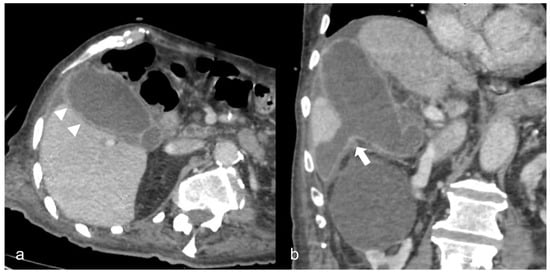

Figure 7. A 69-year-old man with COVID-19 presented a positive Murphy sign. Ultrasound images showed gallbladder wall striation and increased thickness ((b)-arrowheads). The Color Doppler technique revealed hyperemia (a). No gallbladder stones were present indicating acalculous cholecystitis.